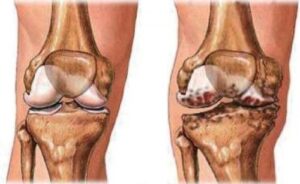

Điều trị thoái hóa khớp gối bằng tiêm chất nhờn

Thoái hóa khớp gối là gì? Thoái hóa khớp là tình trạng tổn thương, thoái hóa...